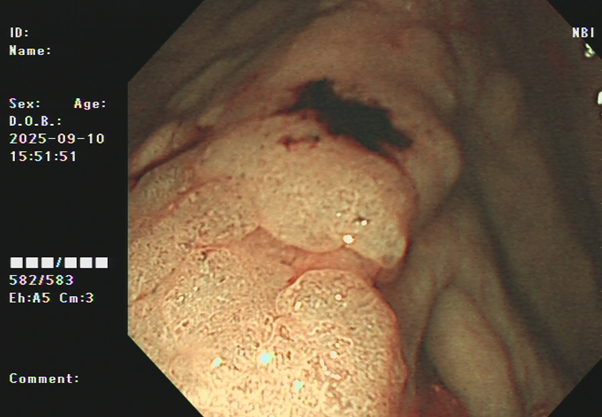

吴姨(化名)平素饮食规则,无腹痛、便血等消化道不适,因其侄女有大肠肿瘤病史,为求安心,特从外地来连州市人民医院进行肠镜检查。消化内镜室吕美光医生在检查中,凭借丰富经验和高清放大染色内镜技术,于盲肠深处发现一个与正常黏膜极其相似、范围达35mmX45mm的平坦微隆起型病灶,并确认其微表面及微血管结构存在异型。后续活检证实,该病灶为盲肠管状腺瘤。

消化内科主任潘新智与患者及家属充分沟通后,为其实施了盲肠黏膜剥离术(ESD)。术中,团队克服了盲肠病变距离肛门远,肠壁薄、蠕动频繁、随呼吸波动大等困难,以微创方法为患者完整切除了盲肠巨大侧向发育型肿瘤,避免了外科手术。

潘新智主任介绍,盲肠侧向发育型肿瘤(LST)是一种发生在盲肠部位的特殊类型的肿瘤,这种肿瘤通常呈扁平状增生,紧贴肠壁,像烙饼一样,具有比普通息肉更高的恶变潜能。由于其特殊的生长方式,盲肠侧向发育型肿瘤在内镜下治疗相对困难,耗时较长,肠道穿孔出血的风险较高,需要医生具备敏锐的观察力和丰富的经验。